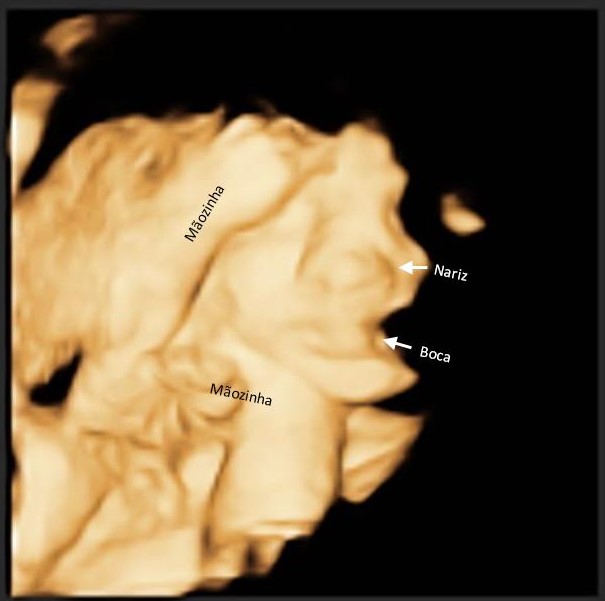

Fizemos a ultra e adivinha? Baby Boy não deixou ver o rostinho, de novo!! A imagem está melhor do que a anterior, mas só dá pra ver a boquinha e o nariz...

Agora é esperar pra ver ao vivo e à cores msm né...papai até falou de tentar fazer na próxima ultra, com 36 semanas, mas acho que é jogar R$ 50,00 no lixo...

Mas graças a Deus ele está perfeitinho, pesando 1.385 kg e medindo 38 cm...desses, 6 cm são só de pé! kkkk O coraçãozinho batendo a 153 bpm, coisa mais fofaa 😍😍